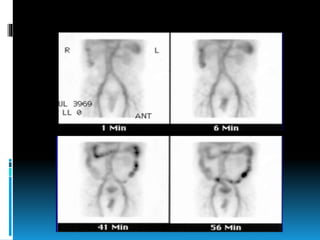

Radionuclide scintigraphy

 Non-invasive

 Done as screening before angiography

 More sensitive

 Detects bleeding as low as 0.1 ml/min

 Major disadvantage false localisation

 Two methods are used

• Technetium Sulfur Colloid

• 99mTc pertechnate-labeled RBC

 Tc-99m Red Blood Cells

• Tc-99m RBCs remain in the vascular

compartment

• In vitro or modified in vivo labeling of RBC is

done

• Allows continuous monitoring of the whole

gastrointestinal tract for a long period

• False-positive readings due to

misinterpretation of intravascular activity and

the possibility of free pertechnetate

accumulation

 sensitivity and specificity of this method are

 Tc-99m sulfur colloid

 Rapid blood clearance of this tracer from

circulation allows for increased detection at

very low bleeding rates (0.05 to 0.1 ml/min)

 Detects bleeding only up to 15 minutes after

intravenous injection